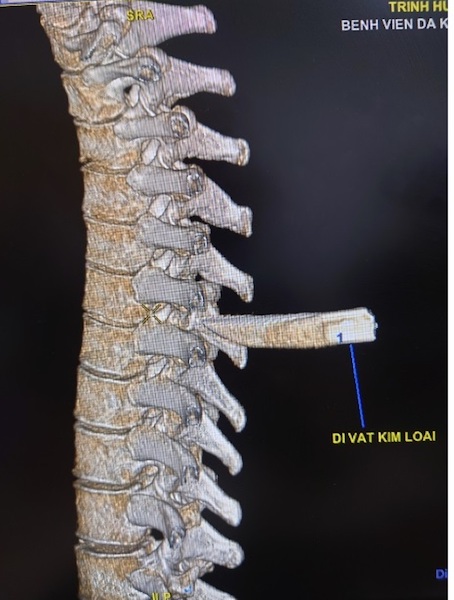

Tình trạng lúc nhập viện, bệnh nhân H. tỉnh, niêm hồng, than đau lưng, khó thở nhẹ với vết thương lưng thành ngực sau cạnh trái cột sống đoạn ngực 4-5 rỉ máu, còn dị vật, không tê yếu chi, dấu hiệu sinh tồn ổn định.

Các bác sĩ khoa Cấp cứu nhanh chóng xử trí cấp cứu và thực hiện các xét nghiệm, siêu âm, chụp Xquang tim phổi thẳng, chụp cắt lớp vi tính lồng ngực… Việc hội chẩn phẫu thuật được ê-kíp bác sĩ khẩn tiến hành và thống nhất phương án xử lý thám sát vết thương và lấy dị vật cấp cứu.

Sau 90 phút phẫu thuật, ê-kíp phẫu thuật gồm: Bs.CK2 Trần Văn Minh – Phó Trưởng, khoa Ngoại Thần kinh, Bs. Nguyễn Châu Thanh, Bs.CK1 Nguyễn Văn Vĩnh – Khoa Phẫu thuật – Gây mê hồi sức đã lấy thành công mũi dao dài 5x2cm ra ngoài.